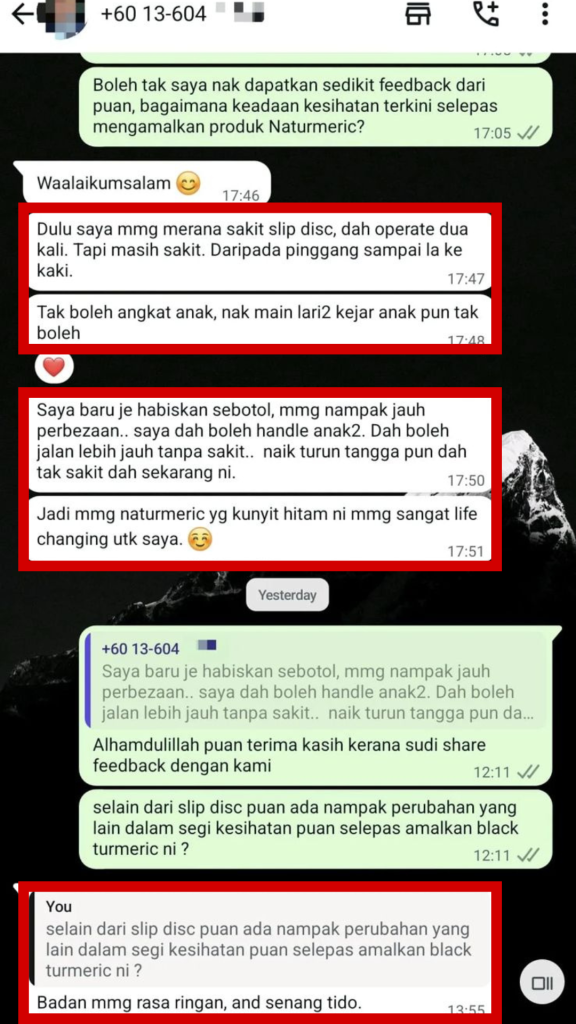

APA KATA MEREKA?

Naturmeric Terbukti Melegakan Secara Semulajadi Tanpa Kesan Sampingan!

"Dah 10 Tahun Menderita RADANG LUTUT STAGE 3. Alhamdulillah lepas amal Naturmeric Black Turmeric.. SAKIT HILANG!"

"Dah 6 Bulan Tanggung DERITA MASALAH SARAF. Alhamdulillah lepas 3 jam, SAKIT HILANG!"

"Dulu selalu sangat LETIH LESU, MENGANTUK. Alhamdulillah amal Naturmeric MAKIN BERTENAGA."

"Pandangan Dr.Zaqrul lepas guna sendiri Naturmeric untuk masalah GOUT. Alhamdulillah cuba Naturmeric DAH TAK KENA GOUT WALAUPUN TAK PANTANG MAKAN."

Ramai dah pilih Naturmeric — kini giliran anda pula rasai bezanya!